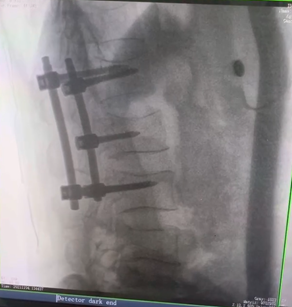

三維C形臂,也叫術(shù)中CT,它可以術(shù)中采集三維圖像,生成類CT斷層圖像及橫斷面圖像,為手術(shù)診斷提供多角度信息,有效輔助術(shù)中植入物定位以及置入結(jié)果檢查。主要適用于骨科、脊柱外科、矯形外科、創(chuàng)傷骨科等科室,尤其適用于復(fù)雜部位的外科手術(shù)。那么,三維C形臂與二維C臂相比,能夠給臨床帶來(lái)哪些優(yōu)勢(shì)呢?

例如治療先天性脊柱側(cè)后凸畸形,由于脊柱自身復(fù)雜的解剖結(jié)構(gòu)限制,使得脊柱外科手術(shù)對(duì)于準(zhǔn)確度有著較高要求。以往我們只能采用傳統(tǒng)的正側(cè)位圖像來(lái)判斷螺釘置入的位置,現(xiàn)在三維C形臂特有的類CT斷層成像,使得治療過(guò)程可視化,立體化,在術(shù)中非常直觀地判斷螺釘植入的準(zhǔn)確度??捎行б龑?dǎo)術(shù)者植入后路螺釘并切除半錐體。同時(shí)可以在術(shù)中實(shí)時(shí)驗(yàn)證手術(shù)效果。有效地縮短了手術(shù)時(shí)間,降低手術(shù)風(fēng)險(xiǎn),避免了不必要的術(shù)后翻修手術(shù)。